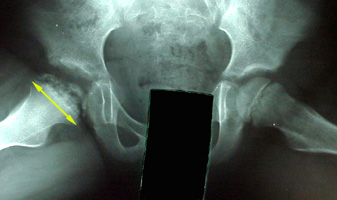

Legg-Calve-Perthes_Disease (3).jpg

الكشف السريري Physical finding

- نقص في مجال حركة مفصل الورك .

- عرج مؤلم .

- في الحالات المتأخرة تكون عضلات الفخذ ضامرة .

تكون عضلات الفخذ وخاصة حول الورك في حالة تقلص . -

- قد يكون هناك نقص في طول الطرف السفلي ناتج عن انضغاط رأس عظمة الفخذ.

- في حالة إصابة كلا الوركين يكون هناك قصر بالقامة .